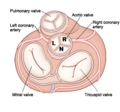

- Aovalv.png 349 × 325; 127 KB

- Aovalv.svg 697 × 633; 58 KB